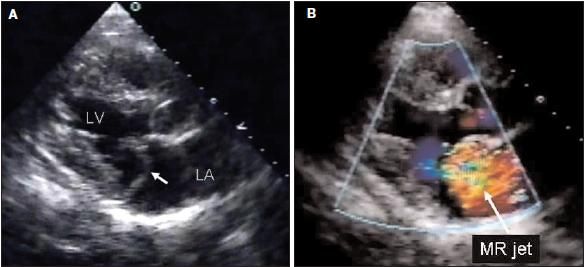

It was learned that the patient had had dental work for placement of a bridge several weeks before presentation to the ED. He was given intravenous penicillin at a dosage of 3 million units every 4 hours. At this time, transesophageal electrocardiography was attempted but was difficult to perform because of the patient's anatomy. A transthoracic ECG confirmed a 3+ mitral regurgitation and a flail posterior mitral valve leaflet; no vegetations were noted (Figure 2). Antibiotic therapy with intravenous ceftriaxone 2 g/d for 8 weeks and gentamicin 70 mg every 8 hours for 2 weeks was initiated. The patient's clinical symptoms improved, and his ESR decreased to 5 mm/h. A repeated MRI scan showed resolving spondylodiscitis at T7-8. He was scheduled for mitral valve repair rather than replacement at another institution.

Figure 2

(A) The arrow in this transthoracic ECG points to the flail posterior mitral leaflet. (B) The arrow in this transthoracic ECG withDoppler flow indicates mitral regurgitation into the left atrium. (LV, left ventricle; LA, left atrium.) (Images courtesy of Natesa Pandian, MD.)